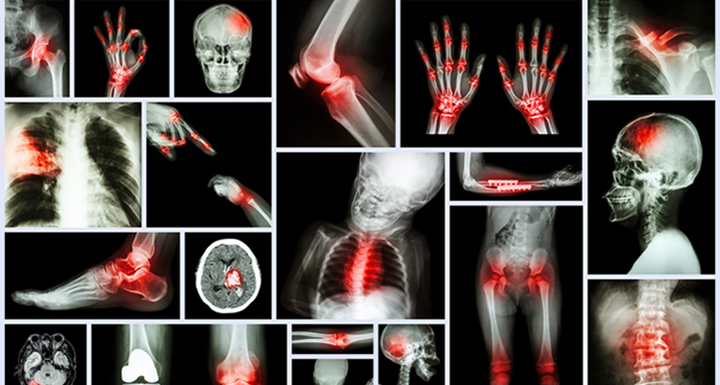

Source: Thinkstock/Dirima

Featured Image Source: Thinkstock/stockdevil